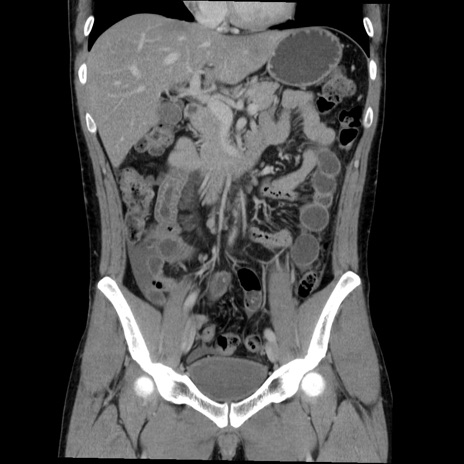

症例36(冠状断像)

【症例】20歳代 男性

【主訴】心窩部痛

【現病歴】今朝より上腹部痛あり。一旦軽快していたが再度出現したため救急要請。昨日夕に白身の魚を含む刺身を食べた。

【身体所見】BP 136/89mmHg、HR 74/min、BT 37.0℃、腹部:膨満、軟、心窩部に圧痛あり。反跳痛なし、筋性防御なし、腸雑音やや亢進あり。

【データ】WBC 17700、CRP 0.48